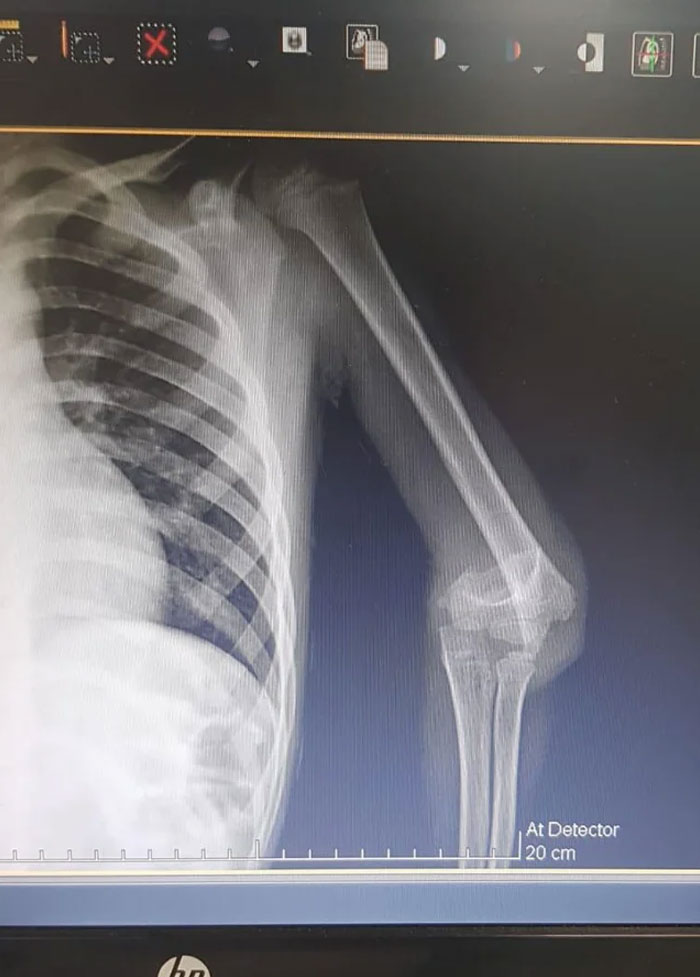

X-Ray From When I Broke My Arm As A Kid

Humeral Fracture

you can cut my arm off doctor! I have another and this looks unsalvageable

X-Ray Of My Femoral Fracture (Yes, The Bone Is Slipt In Two)